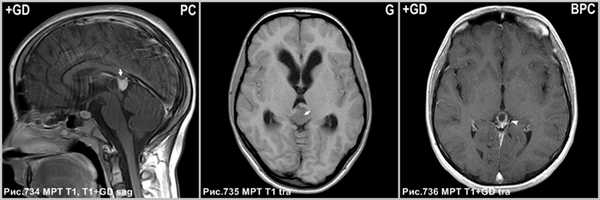

Пинеобластома - первично злокачественная опухоль (как медуллобластома, ретинобластома или эпендимобластома, прежде входила в состав ПНЭО). Опухоль плохо отграничена, имеет инвазивный характер роста. Возникает в возрасте до 20 лет. Содержит кисты и некрозы, обычно крупная на момент первого исследования и осложненная гидроцефалией. Всегда имеются метастазы.

Киста шишковидной железы

Постконтрастное Т1 демонстрирует накопление агента в солидном участке опухоли (стрелки на рис.734). В центре герминомы определяется петрификат (стрелка на рис.735) и отсутствующее обызвествление по периферии. Накопление контраста в стенке кисты шишковидной железы (головка стрелки на рис.736).

В случае с большим размером опухоли возникает сдавление водопровода и развивается окклюзионная гидроцефалия. Пинеоцитомы не сопровождаются гиперактивным половым поведением.

Пинеоцитомы лечатся хирургическим путем и имеют отличный прогноз, когда достигается полная резекция (что бывает почти всегда, поскольку это хорошо отграниченные поражения).

Пятилетняя выживаемость 86%. Были представлены рецидивы и даже лептоменингеальные метастазы, но это редкость. Образование медленно растет, редко приобретает злокачественный тип роста, что проявляется кровоизлияниями, инфильтрацией.

На МРТ это проявляется ↑МР-сигналом по DWI, повышение показателей перфузии и пиком лактат-липидного комплекса на спектроскопии. В крови обнаруживается повышенное содержание мелатонина, основного гормона шишковидной железы.